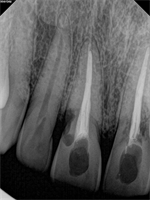

How to Restore Resorption Case?

I have a 35 year old healthy patient who received trauma to #8,9 as a teenager. He is a new patient to me and spoke to him about the radiographic resorptive lesions. His chief complaint is that he is worried about the long term prognosis of the two teeth and if anything should be done...  Read More